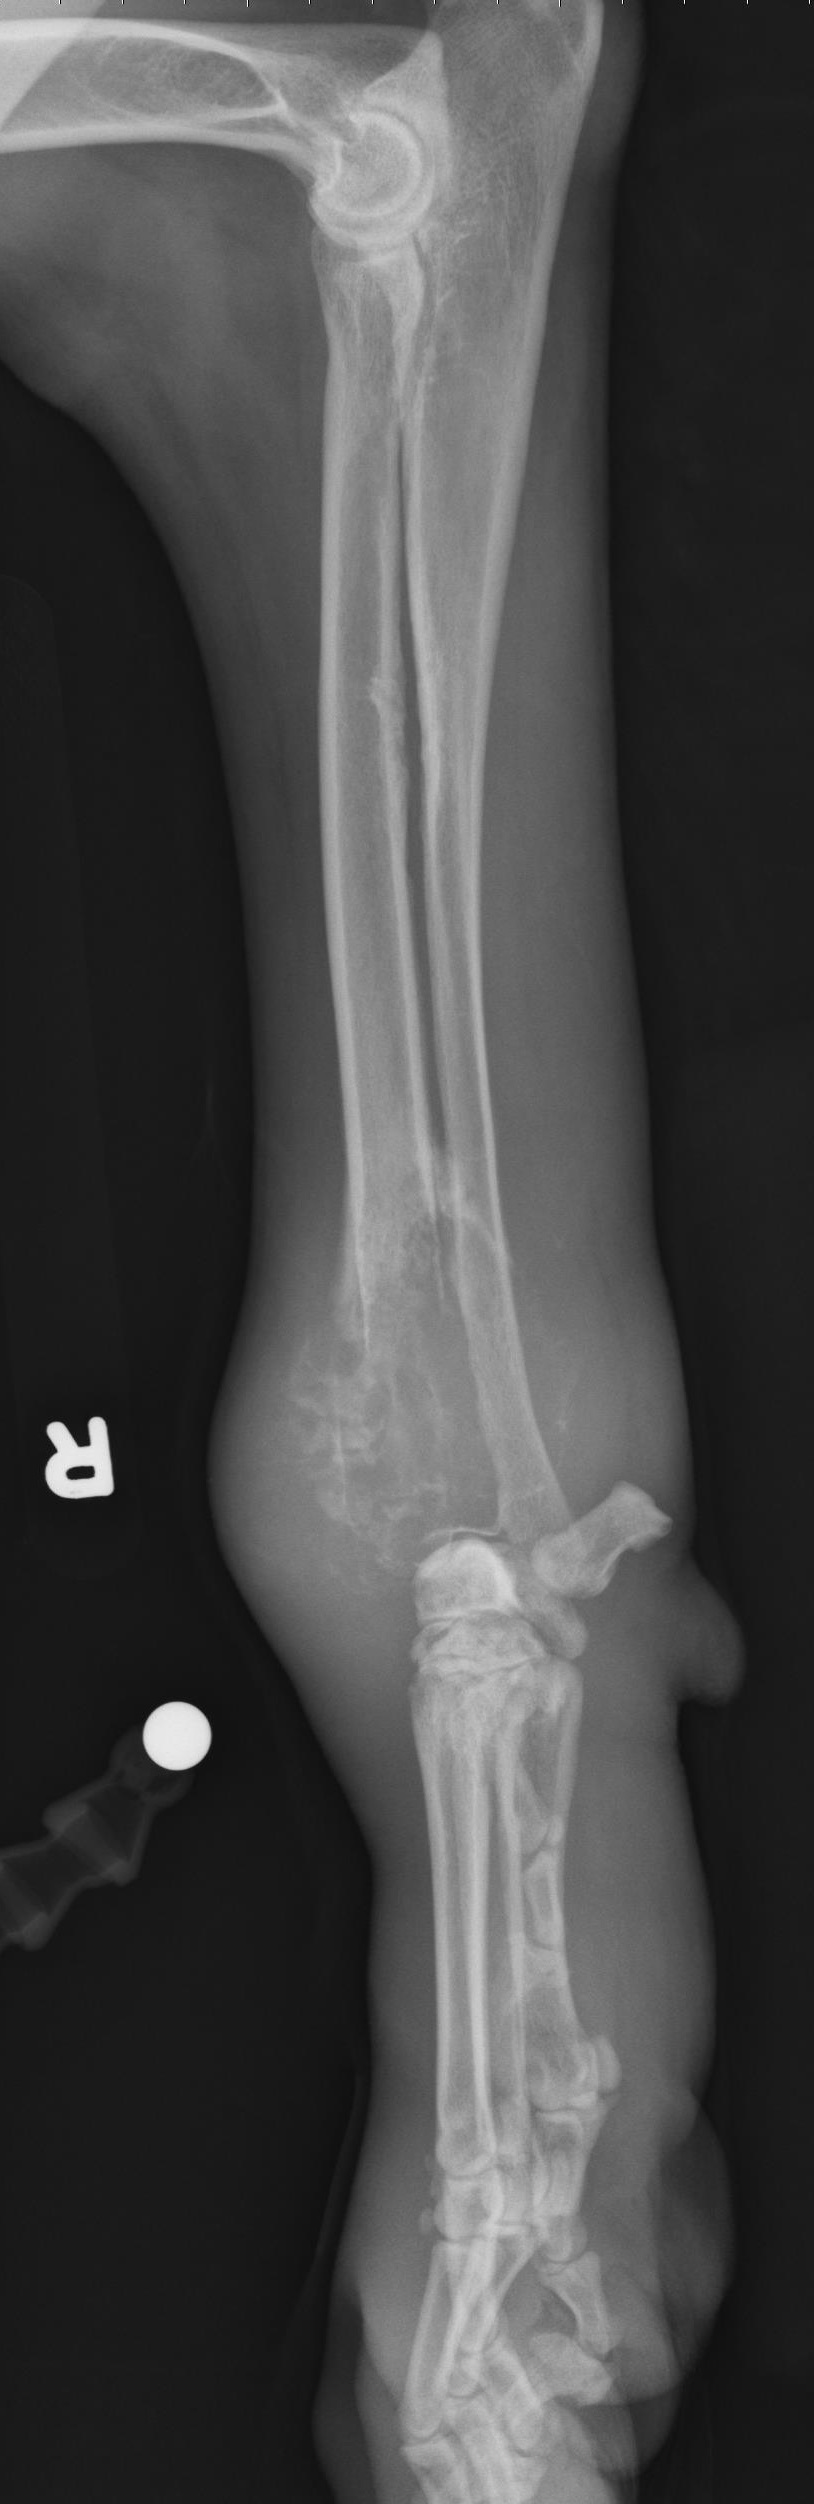

A 6-year old male neutered Weimaraner presents for right forelimb lameness. Radiographs are shown below and show a mixed productive and destructive lesion affecting the right distal radius with accompanying soft tissue swelling. The lesion does not cross the joint. What is the most common primary bone tumor in the dog?

Osteosarcoma

The correct answer is osteosarcoma. Chondrosarcoma, fibrosarcoma and hemangiosarcoma can all be primary bone tumors but are much less common in dogs than osteosarcoma.

Annotations:

Yellow: Amorphous periosteal proliferation

Orange: Geographic lysis and expansile appearance of the mid-radius

Blue: soft tissue swelling